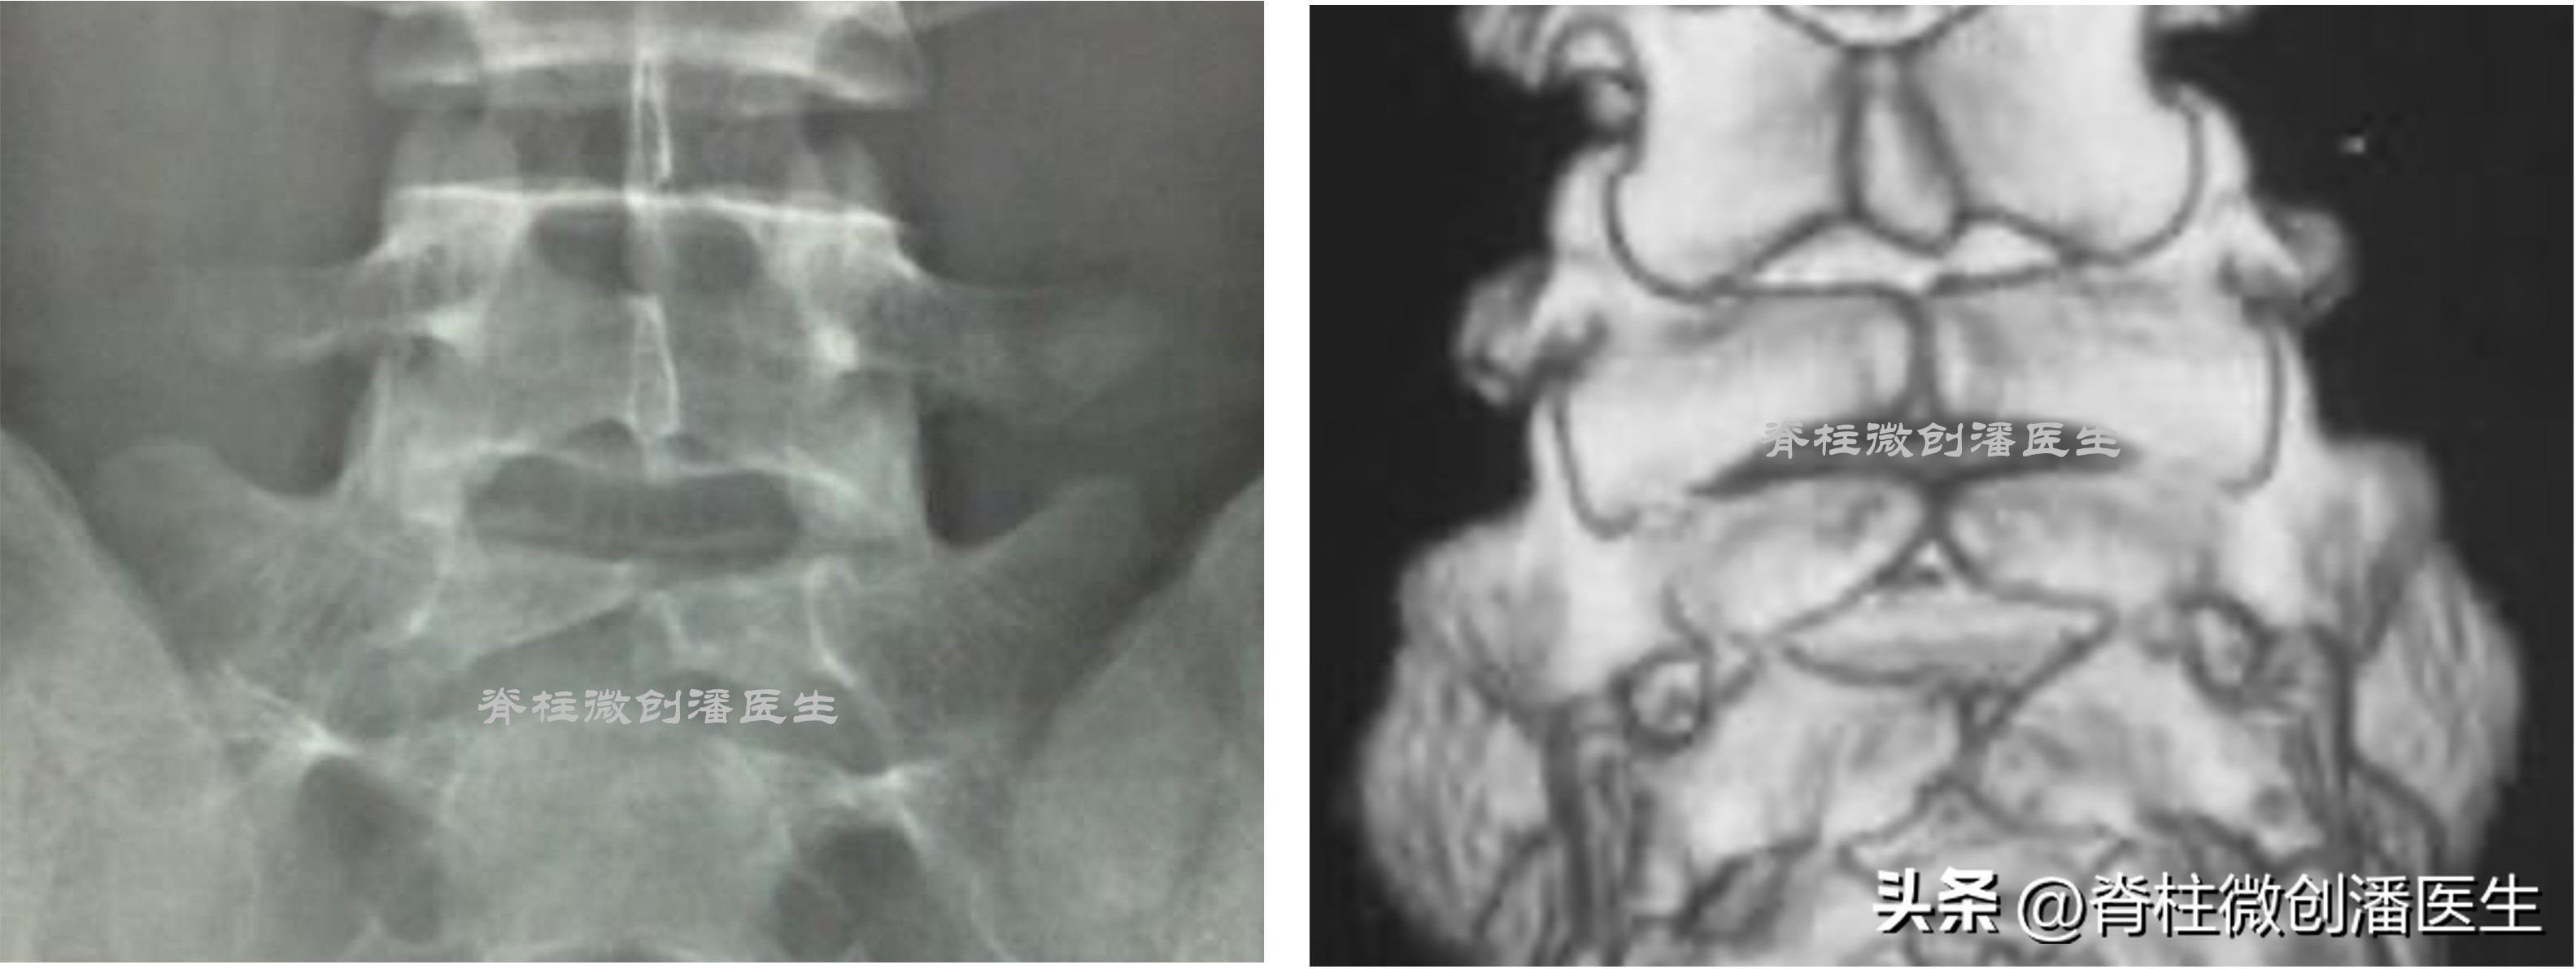

还有一种情况,在第一骶椎隐性脊柱裂时,由于裂隙之间仅有纤维膜相连,腰部后伸时,第五腰椎棘突正好顶在纤维膜上或缺损椎板残余的骨端上,纤维膜与硬脊膜或神经根可发生粘连,因而引起腰痛或出现下肢放射痛。

另外,在脊柱裂部位,两侧椎板之间借纤维膜相连,但在裂隙之间也可为软骨组织所充填,或夹杂一些游离的小骨块。硬脊膜完整无缺,或形成小憩室,并有少量神经纤维分布其中。上述硬脊膜外各种组织均可刺激、压迫、牵张马尾神经根,或与其粘连,从而引起神经症状。